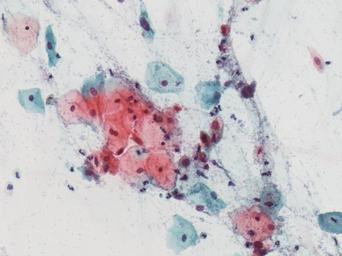

Keywords: lesión intraepitelial escamosa de bajo grado lesiónintraepitelialescamosadebajogrado citología de cuello uterino citologíadecuellouterino citología exfoliativa ginecológica citologíaexfoliativaginecológica citología de cribado citologíadecribado citología anatomía patológica anatomíapatológica bethesda 2001 bethesda2001 osuna cérvix uterino cérvixuterino hpv españa screening lsil enfermedades de transmisión sexual enfermedadesdetransmisiónsexual imágenes de citología ginecológica imágenesdecitologíaginecológica papanicolaou test de papanicolaou testdepapanicolaou tinción de papanicolaou tincióndepapanicolaou drawing Células con núcleo y citoplasma aumentado de tamaño, núcleos irregulares, como plumosos, tendencia al color naranja de muchas células, halos en algunos casos, núcleos dobles en otros, algunos núcleos hipercromáticos. Células con núcleo y citoplasma aumentado de tamaño, núcleos irregulares, como plumosos, tendencia al color naranja de muchas células, halos en algunos casos, núcleos dobles en otros, algunos núcleos hipercromáticos.